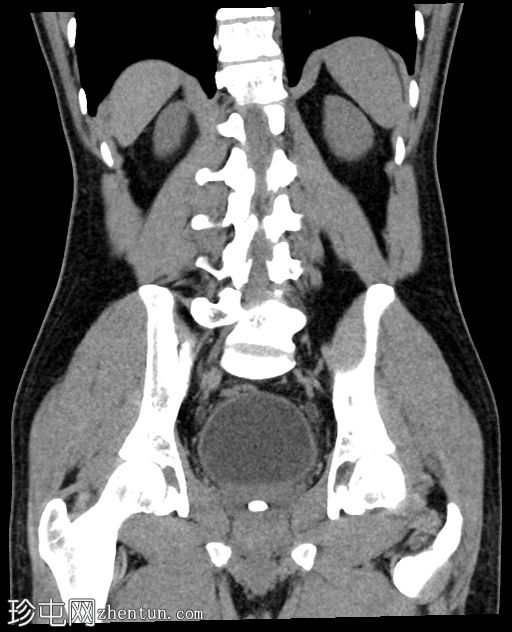

冠状位

平扫

前列腺尿道内可见一枚较大的结石,大小约为10.5 x 13.5 x 7.5 mm(前后径 x 横径 x 头尾径)

轻度肾盂输尿管积水,左侧更为明显

膀胱壁轻度增厚约4 mm,膀胱周围脂肪间隙模糊,提示合并膀胱炎